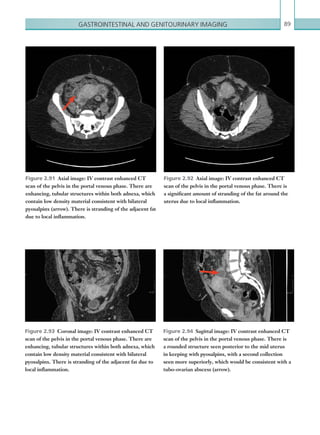

ETT

Central line

Chest drain

NG tube

CT C-SPINE: Odontoid peg#/C1#

Other:

CT ABDOMEN: Free fluid/pneumoperitoneum/liver laceration/splenic laceration/abdominal aorta injury

Lumbar spine #.......................................................................................................................................................................

CT PELVIS – Free fluid/bladder injury

Pelvic #...................................................................................................................................................................................